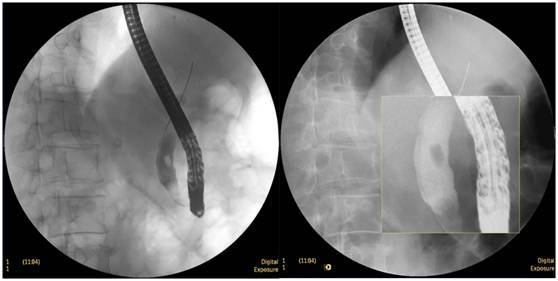

膽囊結(jié)石

ERCP膽囊顯影,見多枚結(jié)石影。

鼻膽管造影

立位注入造影劑,膽總管顯影好,稍擴張,未見結(jié)石影。

膽總管結(jié)石

柱狀球囊擴張完全,膽總管擴張,下段見充盈缺損影。

膽總管擴張,下段見明顯充盈缺損(上圖為反片且局部放大后效果)

柱狀球囊擴張膽總管下段及乳頭(上圖為使用取石網(wǎng)籃取石)。